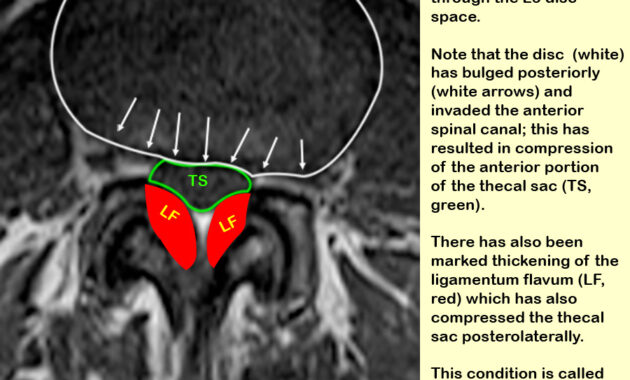

The phrase “mass effect” refers to the pressure exerted by a tumor, herniated disc, or any abnormal growth that intrudes upon anatomical spaces. This effect can distort the thecal sac, much like a boulder disrupting the serene surface of a pond. When such masses accumulate, they may impose compressive forces, leading to a host of neurological implications. The encroachment of these masses can result in the displacement of the thecal sac, which may ultimately compromise the protective environment of the spinal cord.

Diagnosis of mass effect involves a judicious blend of imaging studies, with magnetic resonance imaging (MRI) standing out as the preferred modality. This technology allows for a meticulous visualization of soft tissues and pathologies that may not be sufficiently delineated by conventional radiography. The resulting images act as cartographic representations of the spinal landscape, revealing the location, extent, and nature of any compressive elements.